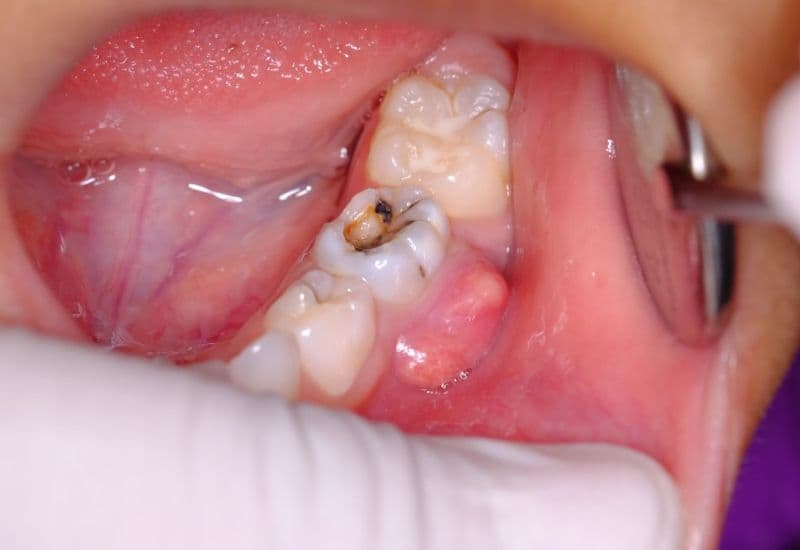

Áp xe răng do sâu răng là giai đoạn nặng của bệnh sâu răng, khi vi khuẩn không chỉ phá hủy men và ngà răng mà còn xâm nhập sâu vào tủy răng, gây viêm nhiễm và tạo mủ quanh chân răng. Áp xe răng có thể xuất hiện ở răng cửa, răng hàm hay bất kỳ răng nào bị sâu nghiêm trọng. Tình trạng này không chỉ gây đau nhức mà còn có nguy cơ lan sang các cơ quan xung quanh nếu không được xử lý kịp thời.

Sâu răng ban đầu chỉ là những lỗ nhỏ trên men răng, nhưng nếu kéo dài mà không được xử lý, vi khuẩn sẽ tiếp tục tấn công sâu vào ngà răng và tủy. Khi tủy răng bị viêm nhiễm, áp xe răng dễ xuất hiện, gây đau nhức dữ dội, sưng nướu, thậm chí lan ra vùng mặt. Việc phát hiện và điều trị kịp thời các lỗ sâu răng là bước quan trọng để ngăn ngừa biến chứng này.